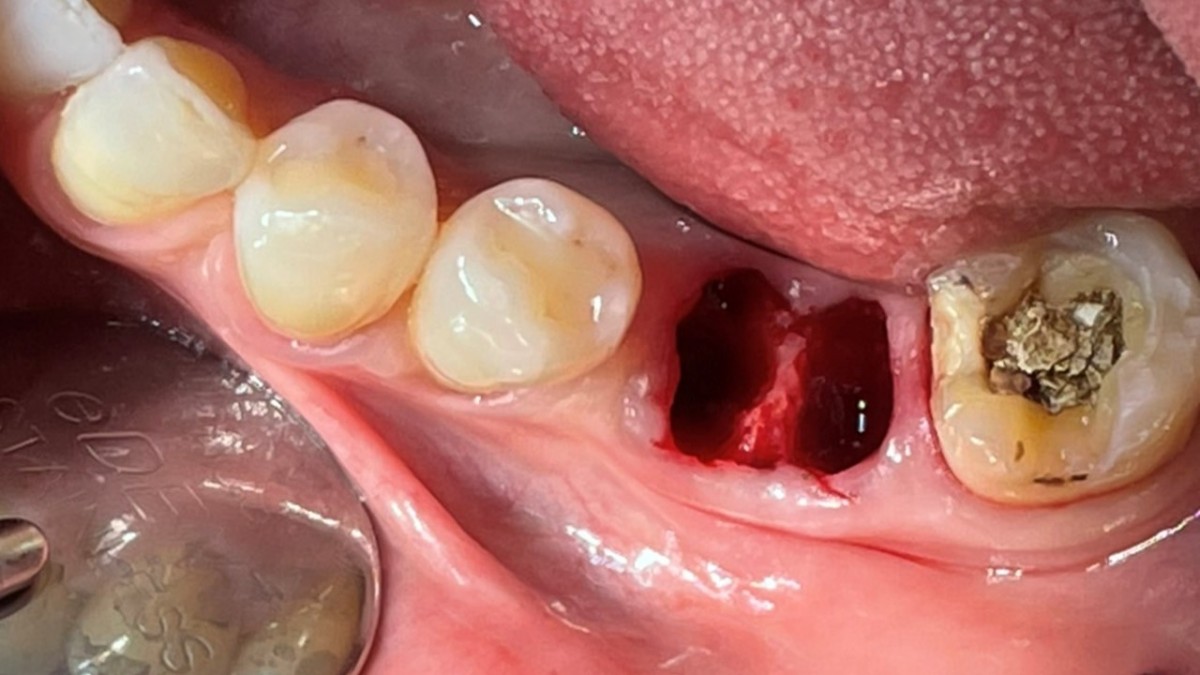

A 51-year-old patient complained of an

old-crowned molar. The lower left molar had a gold crown, and the margin showed discoloration indicative of inner caries. Also, it had furcation-involved periodontitis

with an apical lesion.